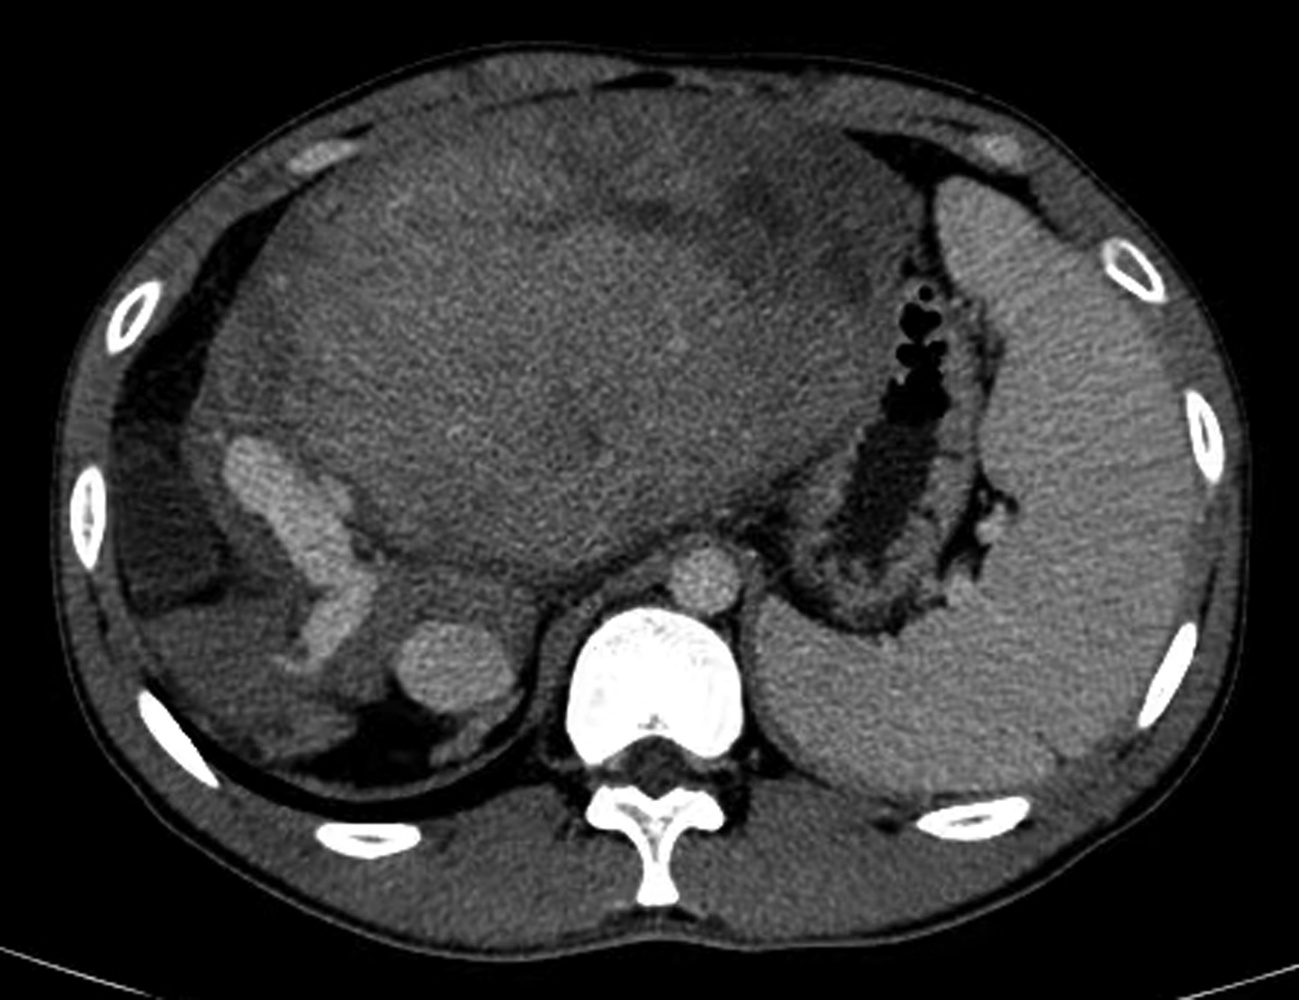

Short-term mortality and death causes after TACE in patients with primary liver cancer

Zhao LIU, Zhi LI, Kailun YANG, Siyin LI, Xiaoli ZHU, Caifang NI

2022, 38(11): 2510-2513. DOI: 10.3969/j.issn.1001-5256.2022.11.014

Abstract(1582) HTML (254) PDF (2070KB)(95)

Abstract:

Objective  To investigate the short-term mortality of transcatheter arterial chemoembolization (TACE) in patients with primary liver cancer, and explore the possible causes of death and countermeasures.  Methods  All patients who underwent TACE at the Department of Interventional Radiology, First Affiliated Hospital of Soochow University from January 2015 to December 2020 were studied, but those with metastatic liver cancer or receiving combined treatment were excluded. The clinical and imaging data of all patients were collected before and 30 days after TACE, and the clinical characteristics of the patients with short-term postoperative death were analyzed. Death within 30 days after TACE was defined as short-term death.  Results  A total of 1466 TACE in 741 patients with primary liver cancer were included. Ten patients (10/741, 1.35%) died within 30 days after TACE, with a mortality rate of 0.68% for all TACE. The mortality rate of d-TACE and c-TACE was 1.62% (3/185) and 0.55 % (7/1281), respectively. The mortality rates of patients at China Liver Cancer Staging Ⅰ, Ⅱ, and Ⅲ stages were 0.45% (2/448), 0.33% (2/599), and 1.43% (6/419), respectively. The mean diameter of the largest lesion in death cases was 10.1±0.8 cm. The possible causes of death were liver failure (4 cases), rupture bleeding (3 cases), myelotoxicity (1 case), pulmonary embolism (1 case), and heart failure (1 case).  Conclusion  The mortality rate after TACE in patients with primary liver cancer is low, with occasional short-term postoperative deaths. The death cases are characterized by a large tumor volume, and the most common causes of short-term death are liver failure and rupture bleeding.